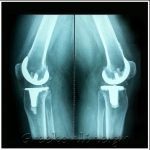

Nέα ΑΡΘΡΟΠΛΑΣΤΙΚΗ ΙΣΧΙΟΥ τύπου ALMIS ελάχιστης επεμβατικότητας και νέα αρθροπλαστική ΓΟΝΑΤΟΣ τύπου επιφανείας, ελάχιστης επεμβατικότητας, με ειδική αξονομέτρηση καθώς και διατήρηση οπίσθιου χιαστού συνδέσμου και ιγνυακού τένοντα για άμεση κινητοποίηση και βάδιση,

“CUSTOM” νέα εξατομικευμένη με έτοιμο εκμαγείο υπερσύγχρονη με προεγχειρητική “Ρομποτική” αρθροπλαστική ΓΟΝΑΤΟΣ,

“ΜΙΝΙ” μονοδιαμερισματική αρθροπλαστική γόνατος για επιγονατιδομηριαία άρθρωση, νέα ημιαρθροπλαστική γόνατος ελάχιστης επεμβατικότητας με κινητό ένθετο ( κινητό τεχνητό “μηνίσκο”) για άμεση βάδιση και άριστο αποτέλεσμα,